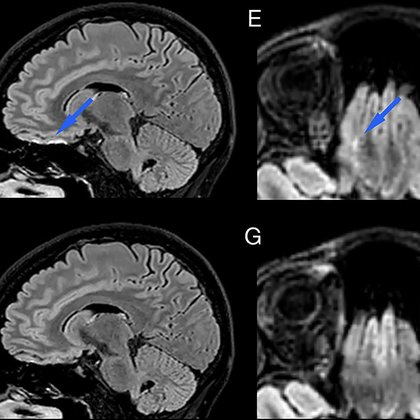

6/9 👥 Human imaging (n = 14 across multiple conditions): C-FLAIR removed skull-base hyperintensity artifacts while preserving lesion visibility in MS and white matter disease ✅ 🩻Key Clinical Point: • SNR unchanged • CNR unchanged

3/9 This is especially noticeable at 3T 🎛️ Skull base, sinuses, and temporal bone regions are notorious for off-resonance and RF variation → where FLAIR is often least trustworthy. Here, the B, F images are acquired without T2-preparation to better expose the FLAIR artifact.